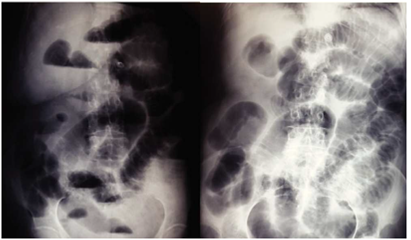

El factor más importante para establecer el diagnóstico de intususcepción secundaria a un lipoma submucoso es considerar la posibilidad del mismo, especialmente en pacientes con síntomas abdominales y episodios previos de suboclusión intestinal.27 El diagnóstico prequirúrgico del lipoma colónico es bastante difícil, debido a la ausencia de síntomas y signos específicos; la realización del mismo amerita el apoyo de estudios de gabinete como son los estudios radiológicos contrastados, la colonoscopia, siendo a veces diagnosticado en el acto quirúrgico.28,29La colonoscopia permite la visualización de la lesión lipomatosa esférica, caracterizada por un crecimiento de la mucosa, de consistencia blanda durante la toma de biopsia y finalmente la visualización de grasa en la misma. El enema baritado es útil para el diagnóstico pero su uso actual es debatible debido al incremento del uso de la tomografía computarizada, que aporta información más detallada.30 En el colon por enema los lipomas aparecen como una tumoración radiolúcida esférica, bien delimitada, que puede fluctuar en forma y tamaño durante su estudio. La radiolucencia y el “signo de la opresión” (cambio en el tamaño y la forma durante la peristalsis) se han considerado patognomónicos de los lipomas colónicos.31,32Sin embargo no es del todo confiable, debido a que si le lesión se encuentra en el colon derecho o está ulcerada es difícil diferenciarla de un tumoración maligna.33 Así mismo el lipoma puede sufrir deformación durante la toma de la biopsia y después retomar su forma original, dato conocido como “signo del cojinete”. En la biopsia, el tejido graso puede protruir a través del sito de la misma dando lugar al llamado “signo de la grasa desnuda”.31

Se trata de paciente femenino de 77 años de edad, con antecedente de hipertensión arterial sistémica, ingresa a nuestro servicio por presentar cuadro doloroso abdominal intenso de una semana de evolución (fig. 1), acompañado de distensión abdominal náusea y vómito, el cual no remitió con la administración de analgésicos, acudió a valoración por facultativo quien solicitó ultrasonograma (USG) abdominal evidenciando la presencia de un tumor en colon derecho, se ingresó a la paciente por presentar persistencia de la sintomatología. A la exploración física hemodinámicamente estable se encontró abdomen distendido, doloroso a la palpación, superficial, media y profunda en cuadrantes abdominales inferiores y ruidos metálicos a la auscultación, con datos de irritación peritoneal. Paraclínicos con leucocitosis leve únicamente. En el USG abdominal reportó en flanco derecho una imagen ecogénica, redondeada, bien delimitada, con medidas de 41 × 38 × 59 mm en sus ejes mayores, la cual a la aplicación de Doppler color no mostró vascularidad, esta zona es aperistáltica, en relación a conglomerado de asas. No se identifica líquido libre. La TAC abdominal (fig. 2) con imágenes compatibles a oclusión intestinal probablemente secundaria a invaginación intestinal a nivel de ciego y colon ascendente, la cual condicionaba ascitis y neumatosis intestinal leve, además de probable adenoma suprarrenal derecho. Con lo anteriormente mencionado se infiere diagnóstico de invaginación intestinal, por lo cual se programa de urgencia para laparotomía exploradora.